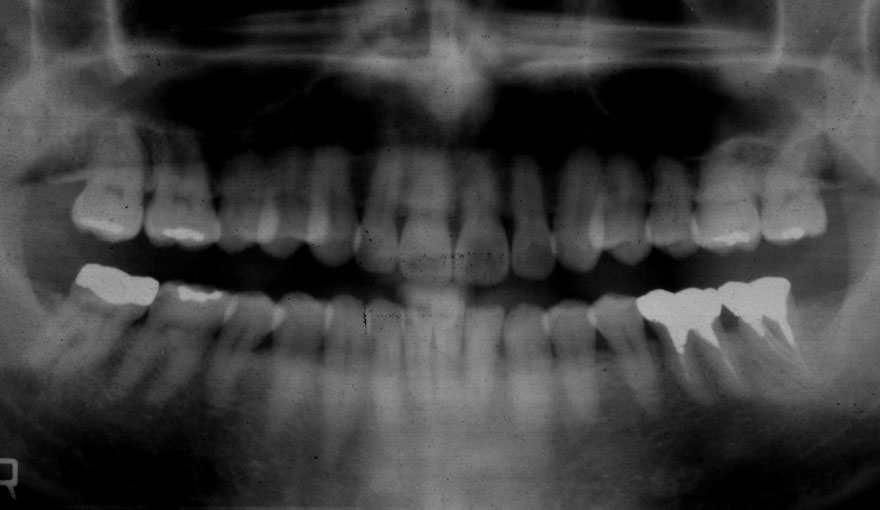

初診時 41歳 男性 平均歯槽骨喪失量:4.11mm

30年後 71歳

平均歯槽骨喪失量:3.70mm

30年間再生量:+0.41mm

年間再生速度:+0.014mm

(ケア頻度:1.27ヵ月ごと)